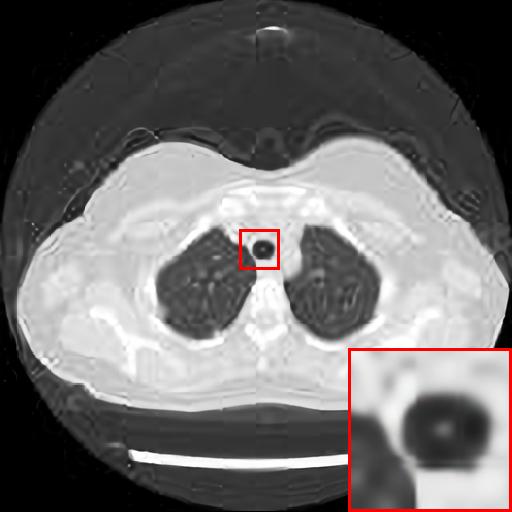

Figure 5: Reconstruction results of each algorithm for low-doze chest CT images.

III-D Super-resolution Reconstruction of Low-dose CT images

Medical pictures, such as computed tomography (CT) scans, are widely used in clinical applications such as noninvasive illness detection, anatomical imaging, and treatment planning, all of which need judgment while doing CT scans. These imaging approaches, however, have some drawbacks. During CT scans, for example, radiation damage is unavoidable. Low-dose CT (LDCT) is currently the clinically recommended strategy for preventing irreversible radiation harm to the body, however it comes at the cost of getting CT pictures with low resolution or noise contamination. The spatial resolution is generally coarser than that of CT imaging in order to get images with a high signal-to-noise ratio. As a result, obtaining high-resolution scanned images with a low-dose CT scanner is now a challenge.

In this section, we selected chest CT images of COVID-19 patients in an actual hospital [26] for our experiments. The visualization results of the experiments are shown in Figure 5 and Figure 6. The experimental results show that our proposed T-GAN is also applicable to the super-resolution reconstruction of low-dose CT images, and the high-resolution images obtained by our model have more detailed information compared with the baseline algorithm.